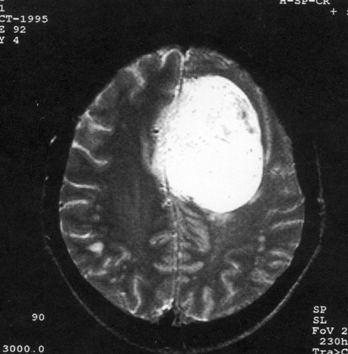

问题 病历摘要:??患者女性,37岁。大便时突起炸裂样头痛3小时,伴喷射样呕吐。既往体健。体检:T37.5℃,BP145/90mmHg,R20次/分,P85次/分。神志清楚,颅神经检查无异常,颈强直,克、布氏征(-),四肢肌力、肌张力正常,病理征(-)。 目前一般认为颅内动脉瘤形成的病因主要有哪些?提示:入院后?10小时行DSA检查,发现前交通动脉瘤